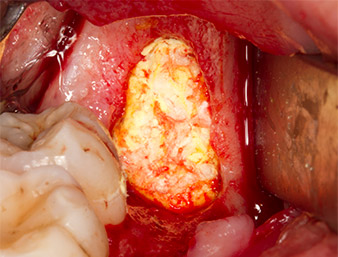

Con el fin de obtener material autógeno para el tratamiento posterior de la herida, se utilizó un inserto piezoquirúrgico (Piezomed B5) para obtener virutas de hueso sano del entorno del resto radicular (figura 5).

Piezomed B5

Imagen 5: Con un inserto piezoquirúrgico con forma de cincel (Piezomed B5) se eleva el hueso en el área de los alvéolos. Tras la retirada del resto radicular, este sirve como material de aumento autólogo (véase figuras 13 y 14).

El tejido autógeno se extrajo con la punta de trabajo en forma de pala del inserto y se guardó en solución salina fisiológica hasta su posterior utilización (véase figura 13).

virutas óseas

Imagen 13: Las virutas óseas procedentes del campo quirúrgico se guardaron en un una solución salina estéril.

A continuación, el tejido óseo autógeno (figura 13) se incorporó en el alvéolo y en el defecto óseo circundante (figura 14). Un velo de colágeno sirvió de protección para el nervio expuesto y cubrió las virutas óseas hasta el nivel del hueso (figura 15). Se aplicaron puntos de sutura con hilos Vicryl de grosor 4.0, que cerraron los tejidos blandos abiertos (figura 16). Tras la operación, se prescribió un preparado de ibuprofeno (Seractil 400 mg 3x1) y un antibiótico con amoxicilina y ácido clavulánico (Augmentine 1g 2x1).

La parte apical del alvéolo

Imagen 14: La parte apical del alvéolo se cubrió con el tejido autógeno.